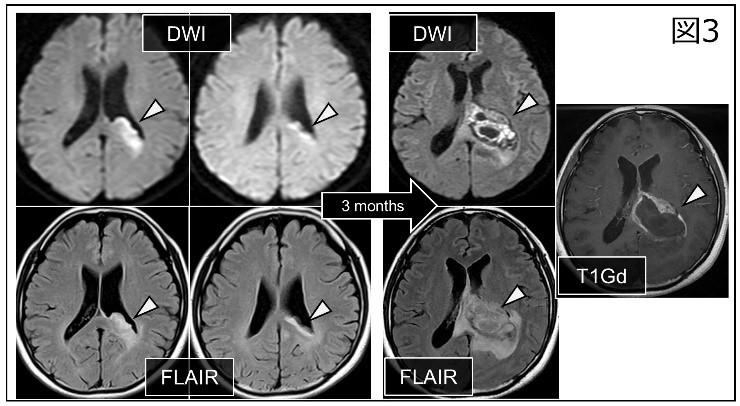

本疑問を解きうる画像が図3になります。脳梁に限局した異常信号が認められ、3か月後にbutterfly glioblastomaに変化していますが、腫瘍成分は脳梁に限局しています。即ち、腫瘍進展を解き明かしうる経時的画像を偶然にも取得できたことで、butterfly glioblastomaが脳梁からも発生しうるのだ、という着想に至りました。確かに、脳梁発生のglioblastomaが存在するのであれば、図2の症例に大脳半球成分がないことの説明がつきます。

【画像解析】図3の様な、経時的画像が全例で得られれば、発生起源がどこであるか1例1例明確に結論付けることができます。実際には、経時的画像の取得はわずか4例で、脳梁発生を示唆するものは図3の1例、大脳半球発生を示唆するものは3例でした。そこで、解析対象となる全80例の各症例において、腫瘍体積を、脳梁部分と大脳半球部分に分けることで、どちらの領域に腫瘍の主体積が存在するかを計算しました。脳梁部体積が腫瘍全体積の50%以上の場合を脳梁タイプ (CC-type, corpus callosum-type)、50%未満を大脳半球タイプ (Hemispheric-type)に分類すると、脳梁タイプの予後が有意に不良であることがわかりました。